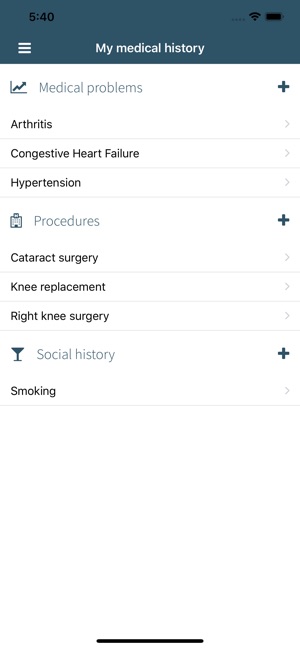

- Manage all your medical problems, procedures, social history and more.